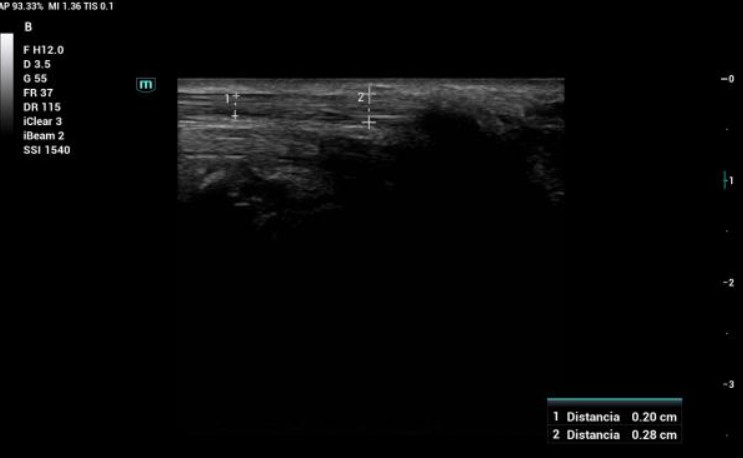

Hallazgos ecográficos

Se identificó un hematoma localizado justo por debajo del nervio mediano, que con la flexoextensión de la muñeca provocaba su compresión. No se realizaron pruebas adicionales. La ecografía clínica fue suficiente para el diagnóstico y manejo.

Hematoma postpunción con compresión dinámica del nervio mediano.

A los 15 días, la paciente refería clara mejoría. La ecografía de control mostró desaparición del hematoma y normalización del área transversal del nervio mediano (9 mm²).